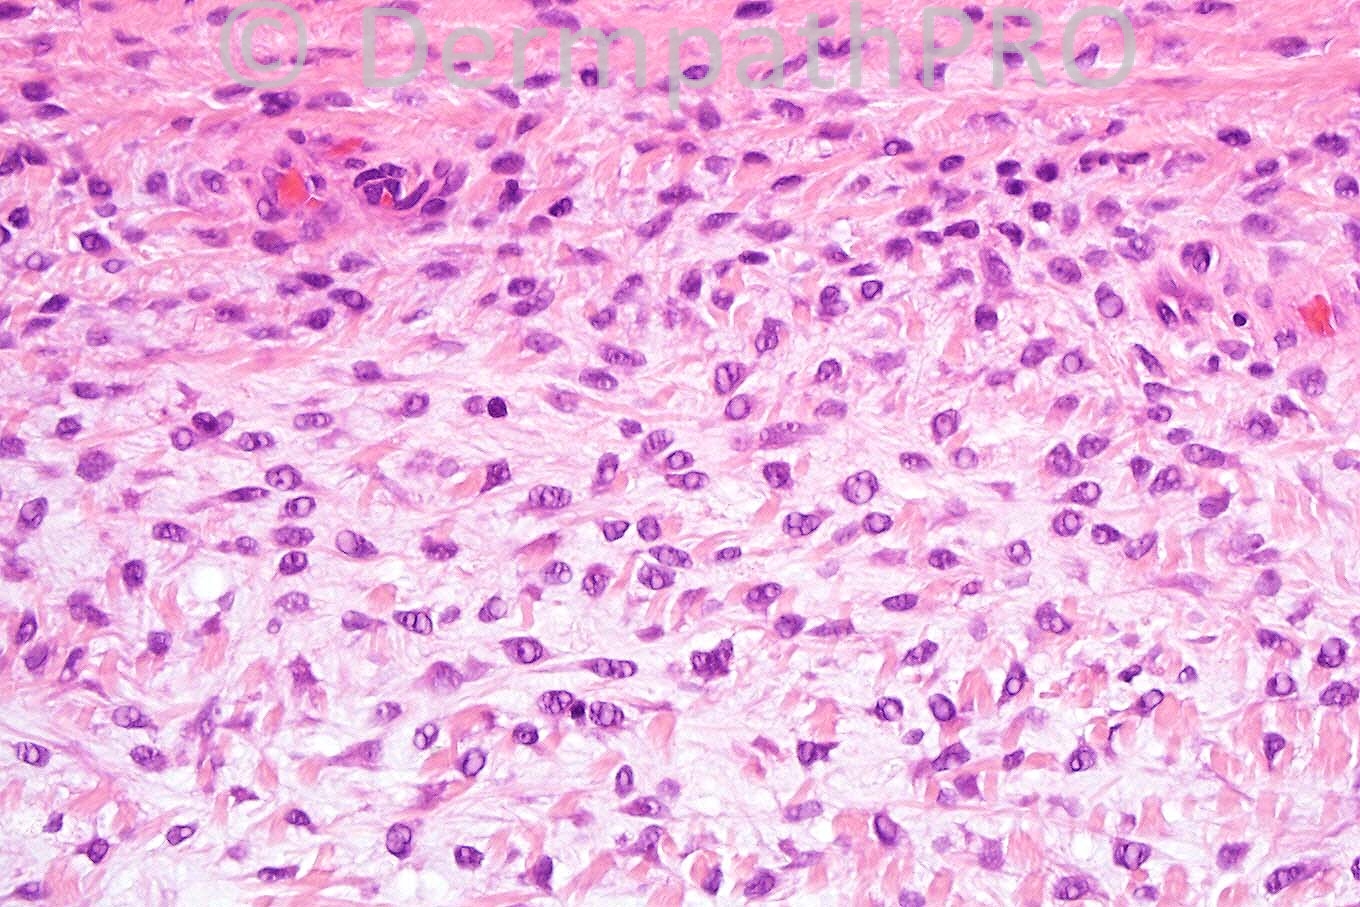

Male 15 years, lesion on eyebrow ? Pilomatrixoma, dermoid cyst.